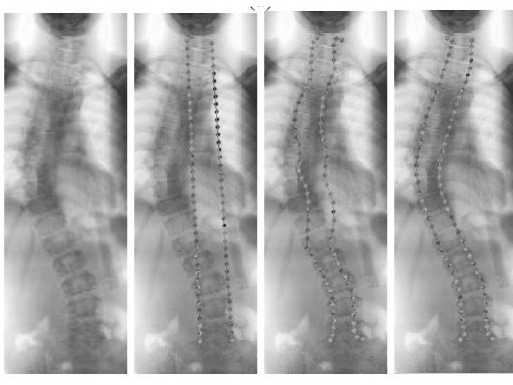

Hasil pengujian metode SCPM. DOK ITS

Metode ini telah diterapkan pada bidang kedokteran, yaitu mendeteksi kelengkungan tulang belakang. Pada pengujian tersebut tampak partikel bermuatan positif bergerak mengikuti bentuk citra tulang belakang penderita skoliosis yang digunakan.

Partikel-partikel membuat segmentasi pada citra tulang belakang dan memudahkan tenaga medis dalam diagnosis. Profesor dari Departemen Teknik Biomedik, Fakultas Teknologi Elektro dan Informatika Cerdas (FTEIC) ini menyebut ke depan SCPM tidak hanya terbatas pada citra tulang.